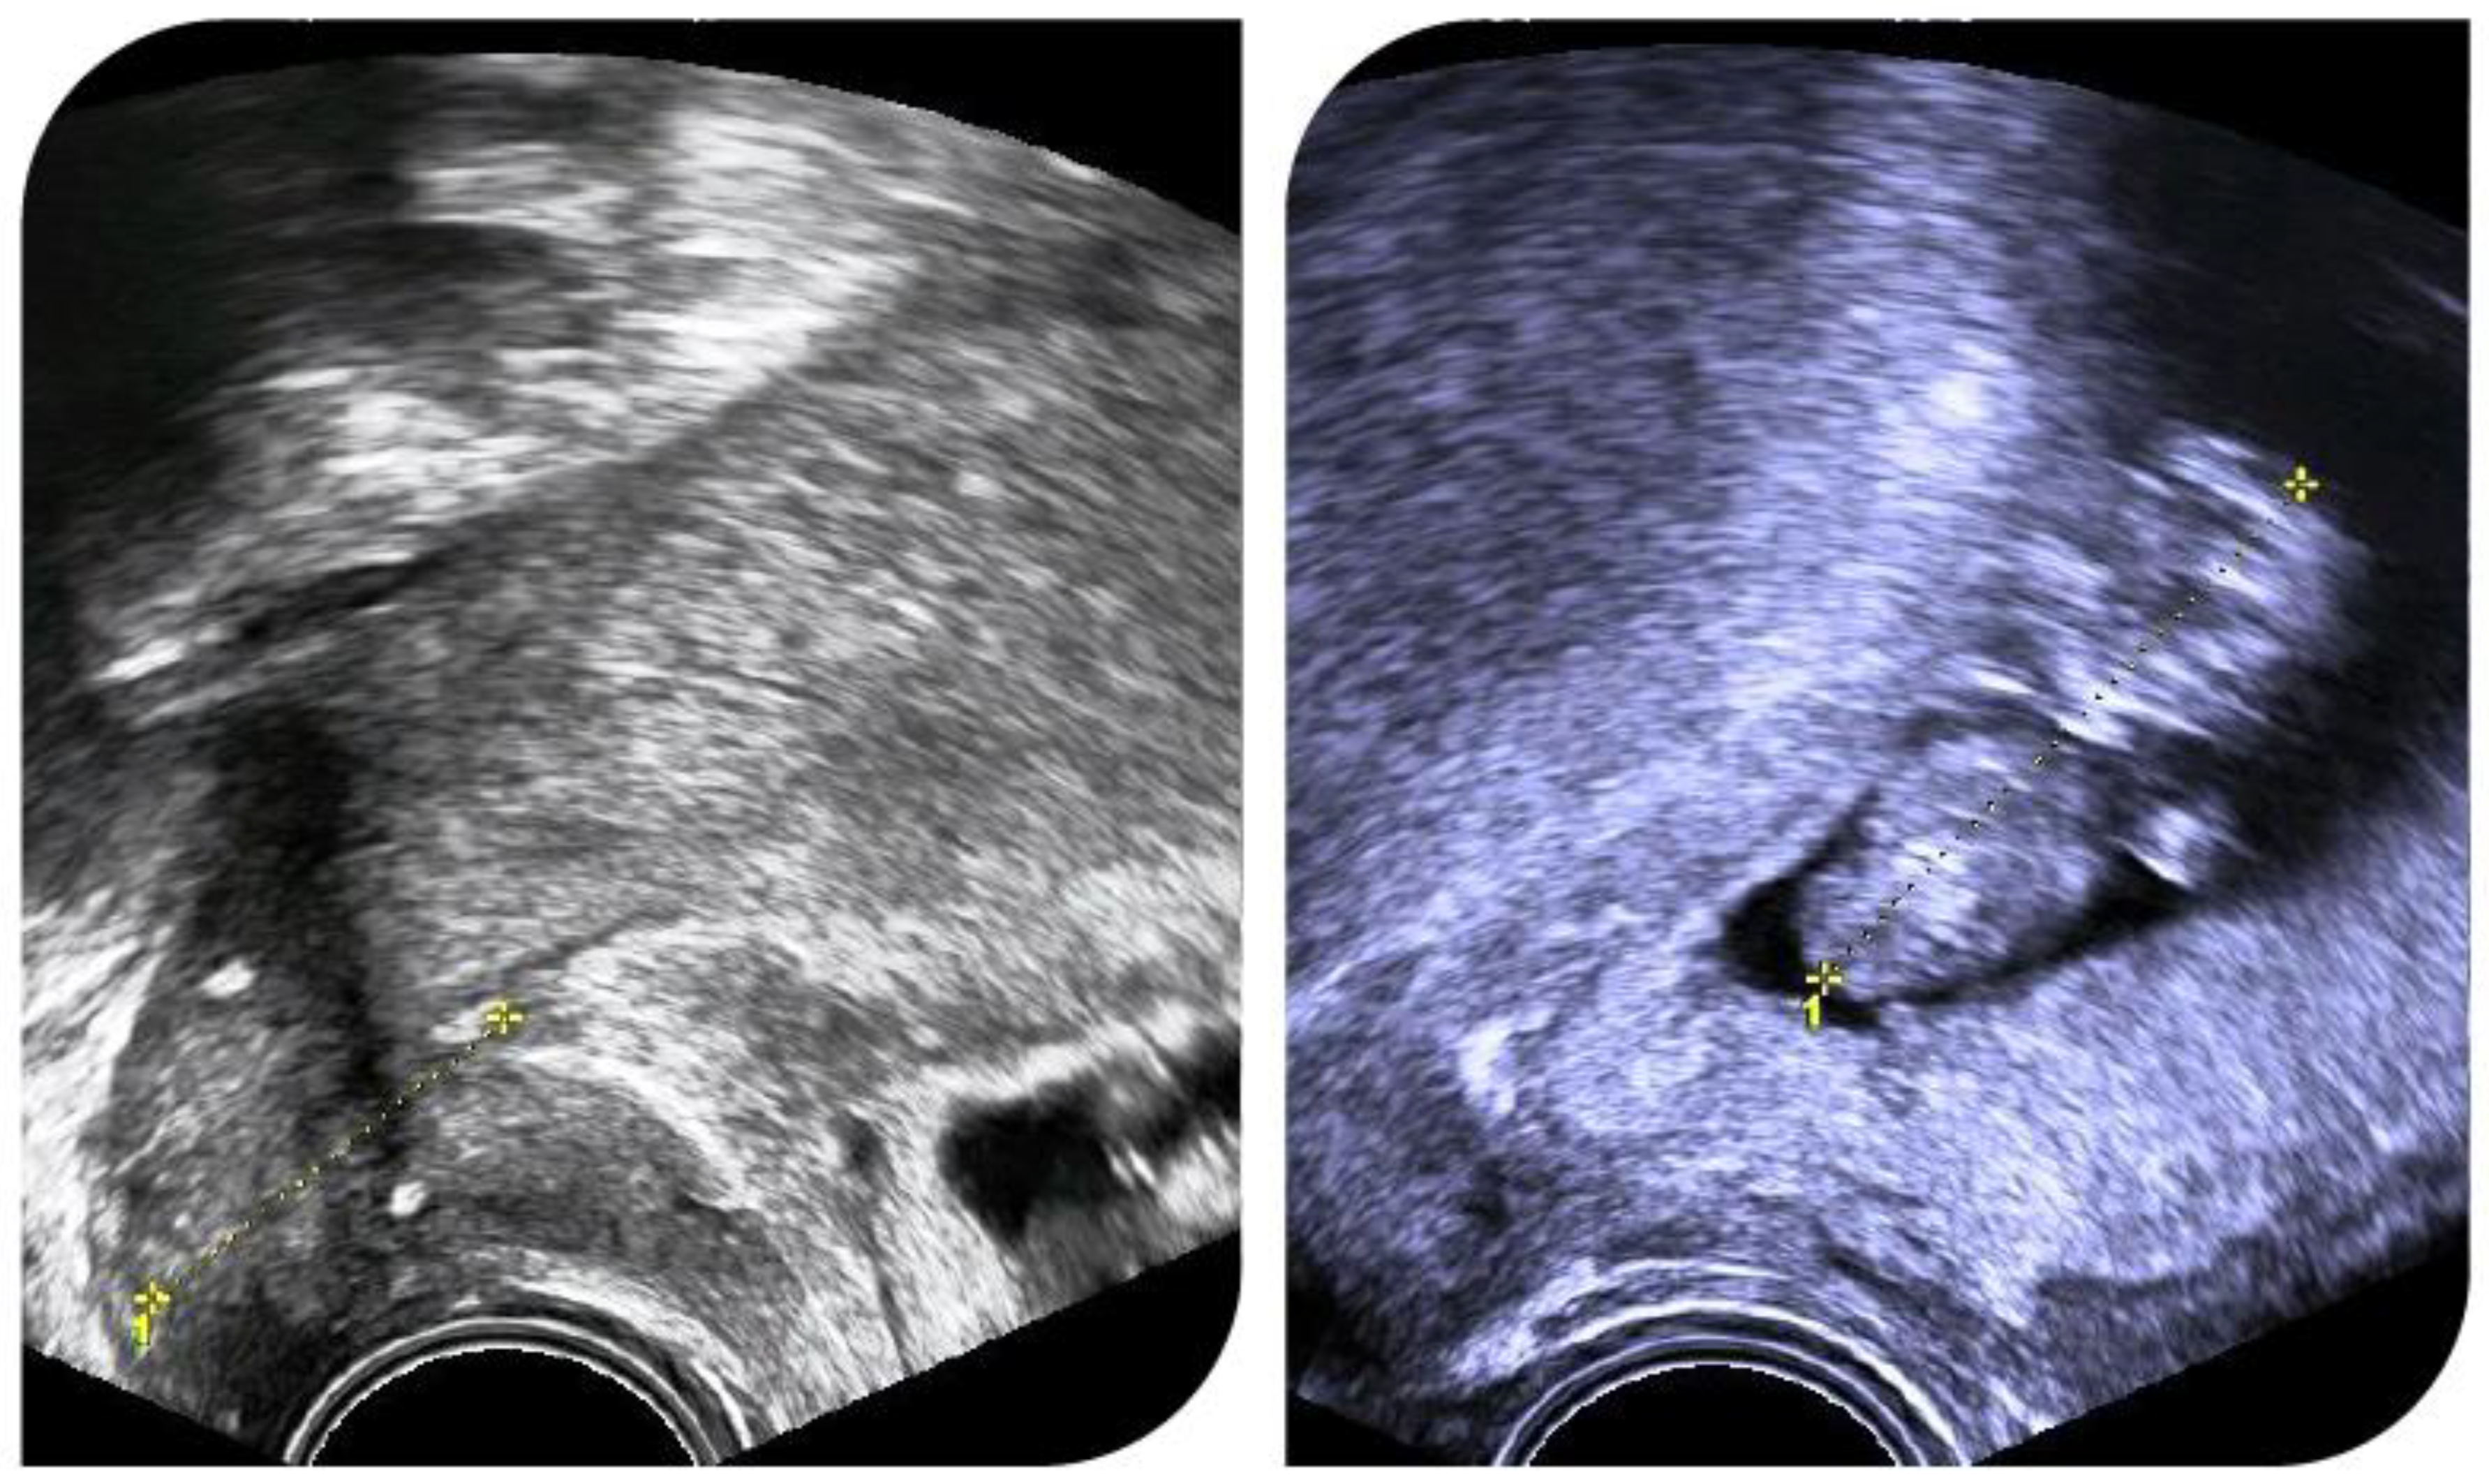

Figure 2 shows ultrasound images of a pregnant patient with cervical length measurements and cerclage position.

Figure 2.

Successful pregnancy after radical abdominal trachelectomy. A cerclage was placed during trachelectomy.